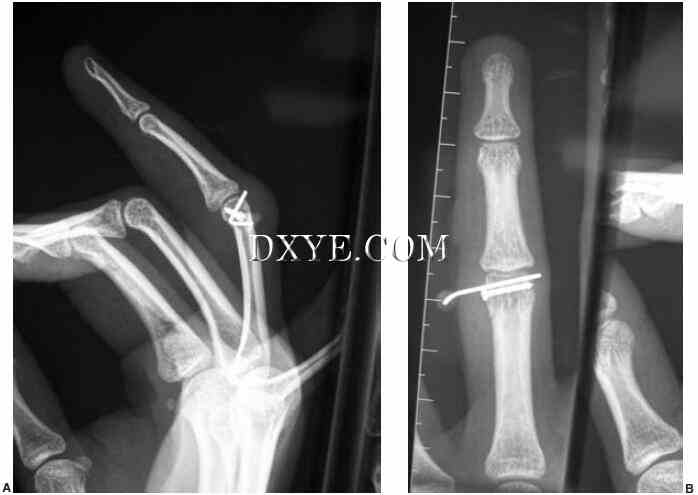

不适合封闭治疗的髁突骨折需要开放的方法。 必须注意不要损伤侧副韧带,因为髁的血液供应源自这种结构。 单髁骨折可通过中轴方法减少。 使用直径为1.0至1.2mm的螺钉来固定。 目标是实现刚性固定,并允许关节的早期运动(图75.14 A和B)。

图 75.14.  近节指骨骨折髁螺钉和克氏针补充。 A. 侧视图。 B. 后前视图。